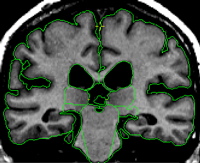

Part II - Posterior portion of the thalamus

The posterior extent of the thalamus is referred to as the pulvinar. The pulvinar extends posteriorly past the VDC and is located just superior and medial to the hippocampus. In this region the pulvinar is egg shaped and grows smaller as you move to the most posterior extent.